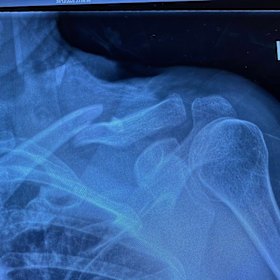

Kerri-Anne Kennerley’s X-ray reveals the broken collarbone after her dramatic fall.Instagram

It took a long time for those in the audience at Pippin to forget the shocking thud Kerri-Anne Kennerley made when she slipped out of the arms of her strong man and crashed to the stage, breaking her collarbone midway through her show-stopping performance.

KAK’s X-ray revealed the full extent of the fracture, which took months of rehab throughout the start of 2021 to recover from. She needed delicate surgery and the insertion of a titanium plate and enough screws to rival the Tin Man.